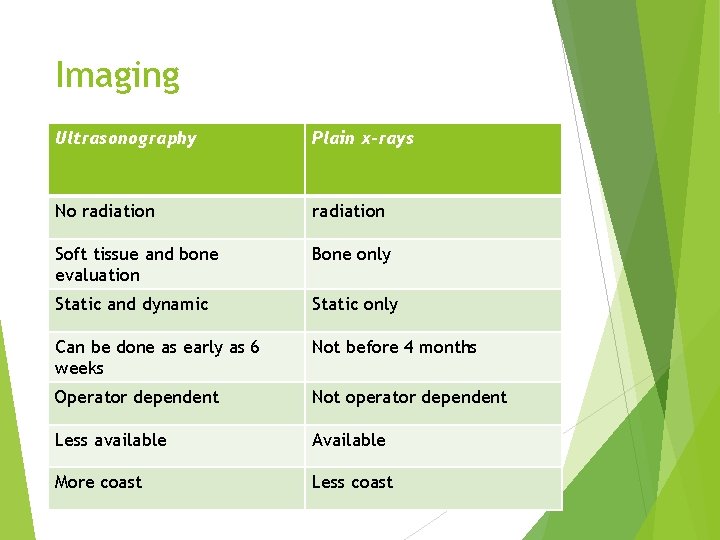

Imaging Ultrasonography Plain x-rays No radiation Soft tissue and bone evaluation Bone only Static and dynamic Static only Can be done as early as 6 weeks Not before 4 months Operator dependent Not operator dependent Less available Available More coast Less coast